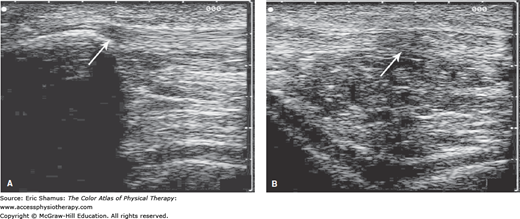

Scenario: A 21-year-old, 6′5″, 190 pound, Division II male collegiate basketball player, with no previous history of knee and/or patellofemoral pathology, reports to the athletic training/sports medicine facility complaining of bilateral anterior knee pain. He states the pain began approximately 2 weeks ago, with the highest incidence of pain occurring in the morning after a weight-training session. About 3 days ago, the pain became constant and has impacted his training. He reported that as part of his off-season conditioning, he has increased strength training (e.g., squats, leg extensions, etc.) and plyometric activities (e.g., box jumps, bounding, etc.) aimed toward increasing power output and vertical jump height. His training over the previous 6 weeks focused on the lower extremity, with 30 to 45 minutes per day of cardiovascular training (e.g., running, cycling) to supplement the 4 days per week of Olympic lifting techniques and plyometric training. He admitted he does not focus on pretraining dynamic warm-ups and performs limited postactivity stretching, but did use ice post activity a few times to manage his pain. The patient presents with no obvious deformity or signs of Osgood–Schlatter disease; no obvious laxity or instability at the patellofemoral joint. Manual muscle testing (eccentric break test) WNL for knee and hip with exception of 4/5 grading: bilateral hip flexion, internal rotation, external rotation, and knee extension. He has a positive Thomas test and positive Ely test, suggesting muscular tightness in his iliopsoas and rectus femoris bilaterally. During gait analysis, he presents with an early heel rise during terminal stance, suggesting tight gastroc-soleus (Achilles tendon). Kinetic chain dysfunction from muscular tightness was further evident during an observed body-weight squat. Radiologic findings include X-rays (negative) and musculoskeletal diagnostic ultrasound (positive for inflammation).